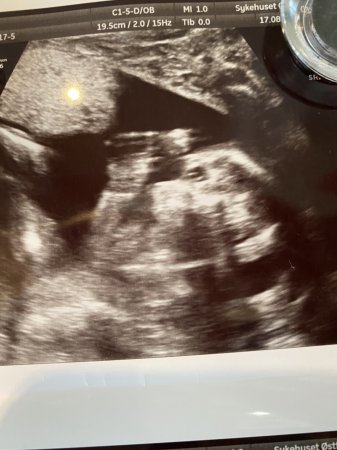

Wow, tenk at du straks er 19 fulgåttesom tiden flyr! Hurra for frisk og fin mageboer, og så koselig at magen er dukket opp

Tenk du er halvveis allerede, tiden går helt latterlig fort![]()

Godt at alt var fint på UL også